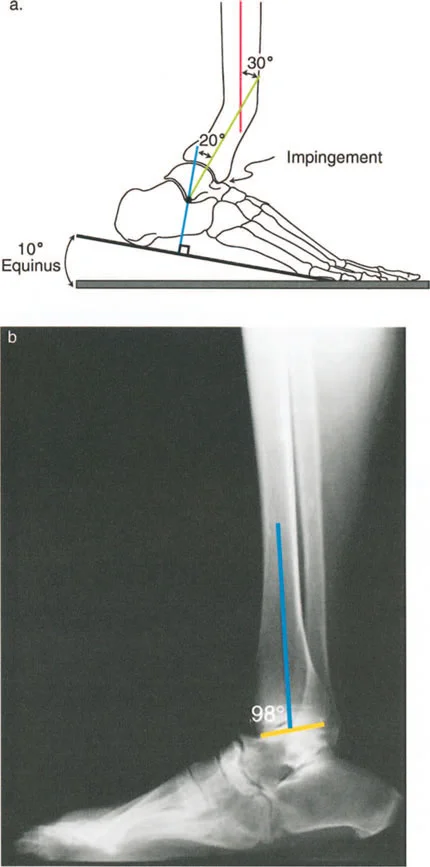

لنأخذ على سبيل المثال، تشوه الانحناء الأمامي (procurvatum) في الجزء البعيد من عظم الساق (الظنبوب) بمقدار 20 درجة. في تشوه الانحناء الأمامي (القمة الأمامية)، يميل السطح المفصلي البعيد لعظم الساق (plafond) إلى الأعلى (ظهريًا). لتحقيق قدم مستوية (plantigrade foot) على الأرض أثناء مرحلة الوقوف، يجب على المريض استهلاك مدى حركة البسط الظهري المتاح للكاحل فقط لاستيعاب العظم المنحني.

يتطلب التقدم الأمامي الطبيعي للجسم فوق قدم ثابتة ما لا يقل عن 10 درجات من البسط الظهري للكاحل خلال مرحلة دوران منتصف القدم. إذا استهلك تشوه الانحناء الأمامي بمقدار 20 درجة كل البسط الظهري المتاح لمجرد تسطيح القدم، فلن يتبقى أي بسط ظهري لمرحلة دوران منتصف القدم. سيؤدي ذلك إلى انحشار الحافة الأمامية للسطح المفصلي لعظم الساق البعيد مباشرة ضد عنق عظم الكاحل (talus).

النتيجة الحركية: نظرًا لأن عظم الساق لا يمكنه الدوران إلى الأمام فوق الكاحل، يجب على المريض تقصير طول خطوة الساق الطبيعية المقابلة بشكل مصطنع. علاوة على ذلك، للحفاظ على مركز الثقل يتحرك إلى الأمام دون السقوط، سيدفع المريض ركبة الساق المصابة بقوة إلى الخلف، مما يؤدي إلى فرط تمدد تعويضي (hyperextension) في الركبة من نفس الجانب. بمرور الوقت، يؤدي هذا الفرط الديناميكي في تمدد الركبة إلى تمدد المحفظة الخلفية ويمكن أن يؤدي إلى ألم شديد في الجزء الأمامي من الركبة، وانحشار الوسادة الدهنية، وأمراض الغضروف الهلالي.

يحدث التحميل غير الطبيعي أيضًا نتيجة للتضحية بحركة المفصل في المستوى السهمي. لننظر إلى تشوه الركبة الخلفية (recurvatum) في الجزء البعيد من عظم الساق (القمة الخلفية). لتسطيح القدم، يجب على المريض التعويض عن طريق ثني الكاحل بشدة (plantarflexion). يؤدي هذا الانثناء التعويضي إلى كشف الجزء الأمامي من قبة عظم الكاحل.

تظهر الأبحاث أن ما لا يقل عن 5 درجات من الركبة الخلفية مع الانثناء التعويضي يقلل من منطقة التلامس بين عظم الساق وعظم الكاحل بنسبة مذهلة تصل إلى 30%. وفقًا للفيزياء الأساسية (الضغط = القوة / المساحة)، فإن تقليل منطقة تحمل الوزن بنسبة 30% مع الحفاظ على نفس حمل وزن الجسم يزيد بشكل كبير من الضغط لكل وحدة مساحة على الغضروف المتبقي. يؤدي هذا الحمل المركز على الجزء الأمامي من مفصل الكاحل حتمًا إلى تآكل الغضروف الميكانيكي والتهاب مفصل الكاحل المبكر.